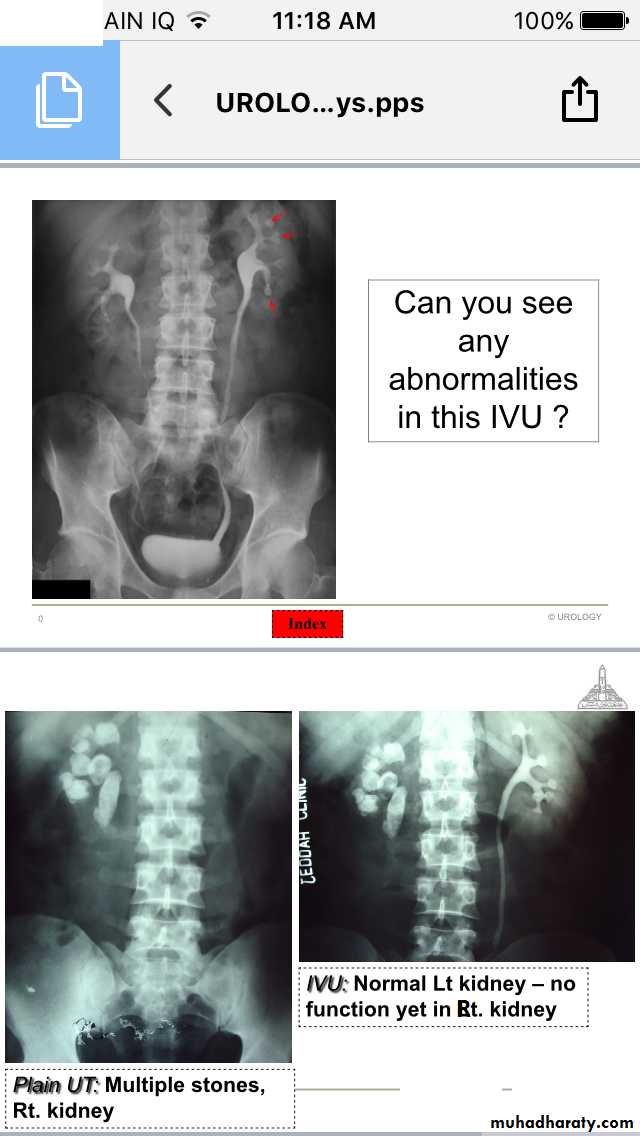

IVU

Renal stones